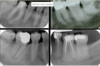

is the following periapical pathology or not?

yes

83

yes - root filled - PDL isnt continuous - lamina dura isnt continuous

84

no

85

86

yes - it is crowned - apical radiolucency - lamina dura tracking off